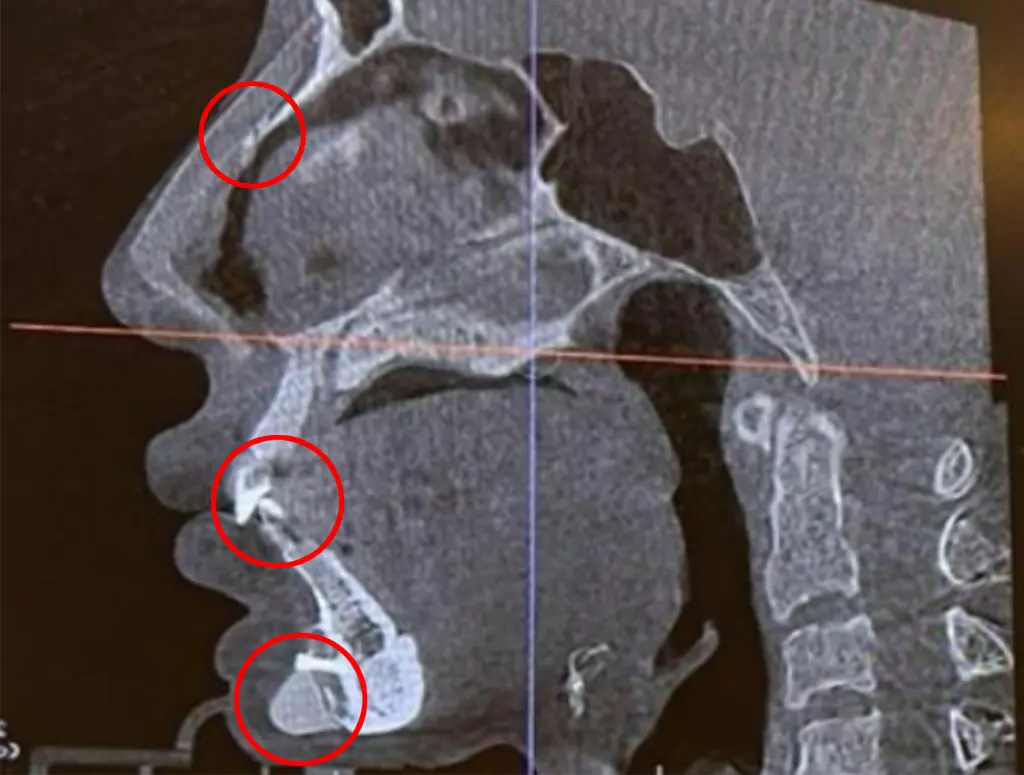

Рентгеновский снимок, показывающий три винта на лице Фанга.

На сопроводительных фотографиях видно, что один из болтов расположен над ее губой и направлен вниз, а другой — в нос.

При попытке пройти через сканер безопасности в аэропорту машина обнаружила 1-дюймовый хирургический винт чуть ниже ее нижней губы, как видно на ее фотографиях в Instagram.

Фанг считает, что винт остался там во время «протеза подбородка», который она получила восемь лет назад.